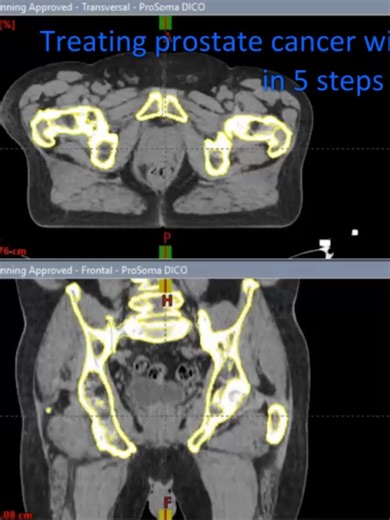

Radiation Therapy Treatment Plan

Stereotactic Body Radiotherapy fo